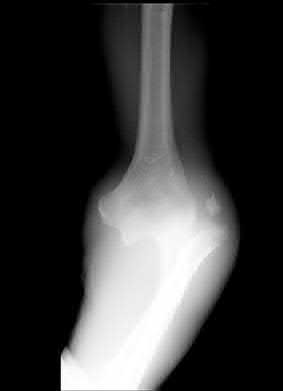

A 26-year-old male sustains an elbow injury after a fall from a skateboard resulting in valgus and supination forces across the left elbow. A CT scan of the left elbow is shown in Figures A through D. This fracture pattern is most commonly associated with what other traumatic elbow pathology?

The clinical presentation is consistent with a coronoid tip fracture. This fracture pattern is associated with a radial head fracture and posterolateral ulnohumeral dislocation - together making up the terrible triad injury.

A terrible triad injury is the result of a valgus and supination injury and involves posterolateral elbow dislocation or lateral collateral ligament injury, radial head fracture, and fracture of the coronoid process. The elbow may dislocate postero-laterally with the anterior bundle of the MCL intact, but if the MCL is injured it is typically the last structure to fail. The coronoid fracture is typically a small fragment isolated to the tip. This is a result of a posteriorly directed force driving the coronoid into the trochlea prior to posterior elbow dislocation. CT scan is a useful modality when small or comminuted fragments are difficult to visualize on plain radiographs.

Figures A through D show consecutive 2.00 mm sagittal CT reformats demonstrating a small coronoid fracture fragment which was addressed with suture fixation.